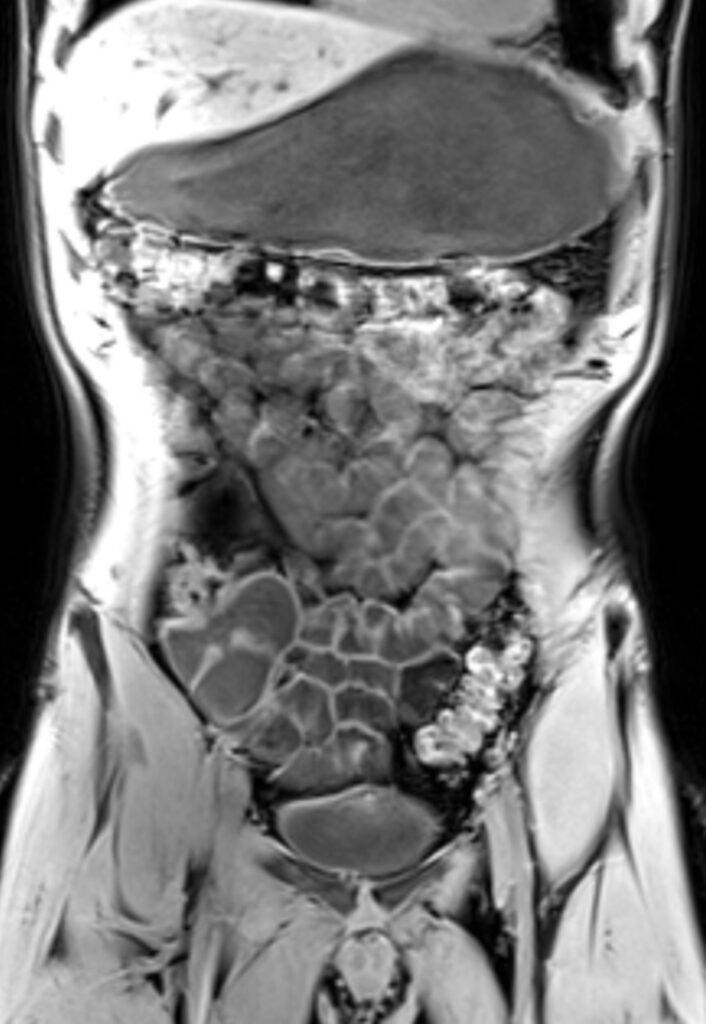

Was kann man auf einer MRT des Abdomens sehen?

Auf einer MRT-Aufnahme sind insbesondere die Organe im Bauchraum sichtbar, da Weichteile in einer MRT sehr gut abgebildet werden können.

Zu sehen und später im weiteren Verlauf beurteilbar sind:

- Leber, Gallengängen, Bauchspeicheldrüse, Nieren und Nebennieren mit Harnleiter, Milz, Becken

Durch die detailreichen Abbildungen können Veränderungen der Organe festgestellt werden, die auf bestimmte Krankheiten schließen lassen – so können beispielsweise Entzündungen oder Gewebsveränderungen im Bauchraum festgestellt werden.

Es kann zwischen gut- und bösartigen Tumoren unterschieden werden. Dies ermöglicht eine genaue Diagnose, woraufhin ein schnelles und geeignetes Therapieverfahren angesetzt werden kann.

Auch bei diffusen und nicht lokalisierbaren Schmerzen im Bauchraum kann eine MRT- Untersuchung Klarheit schaffen.